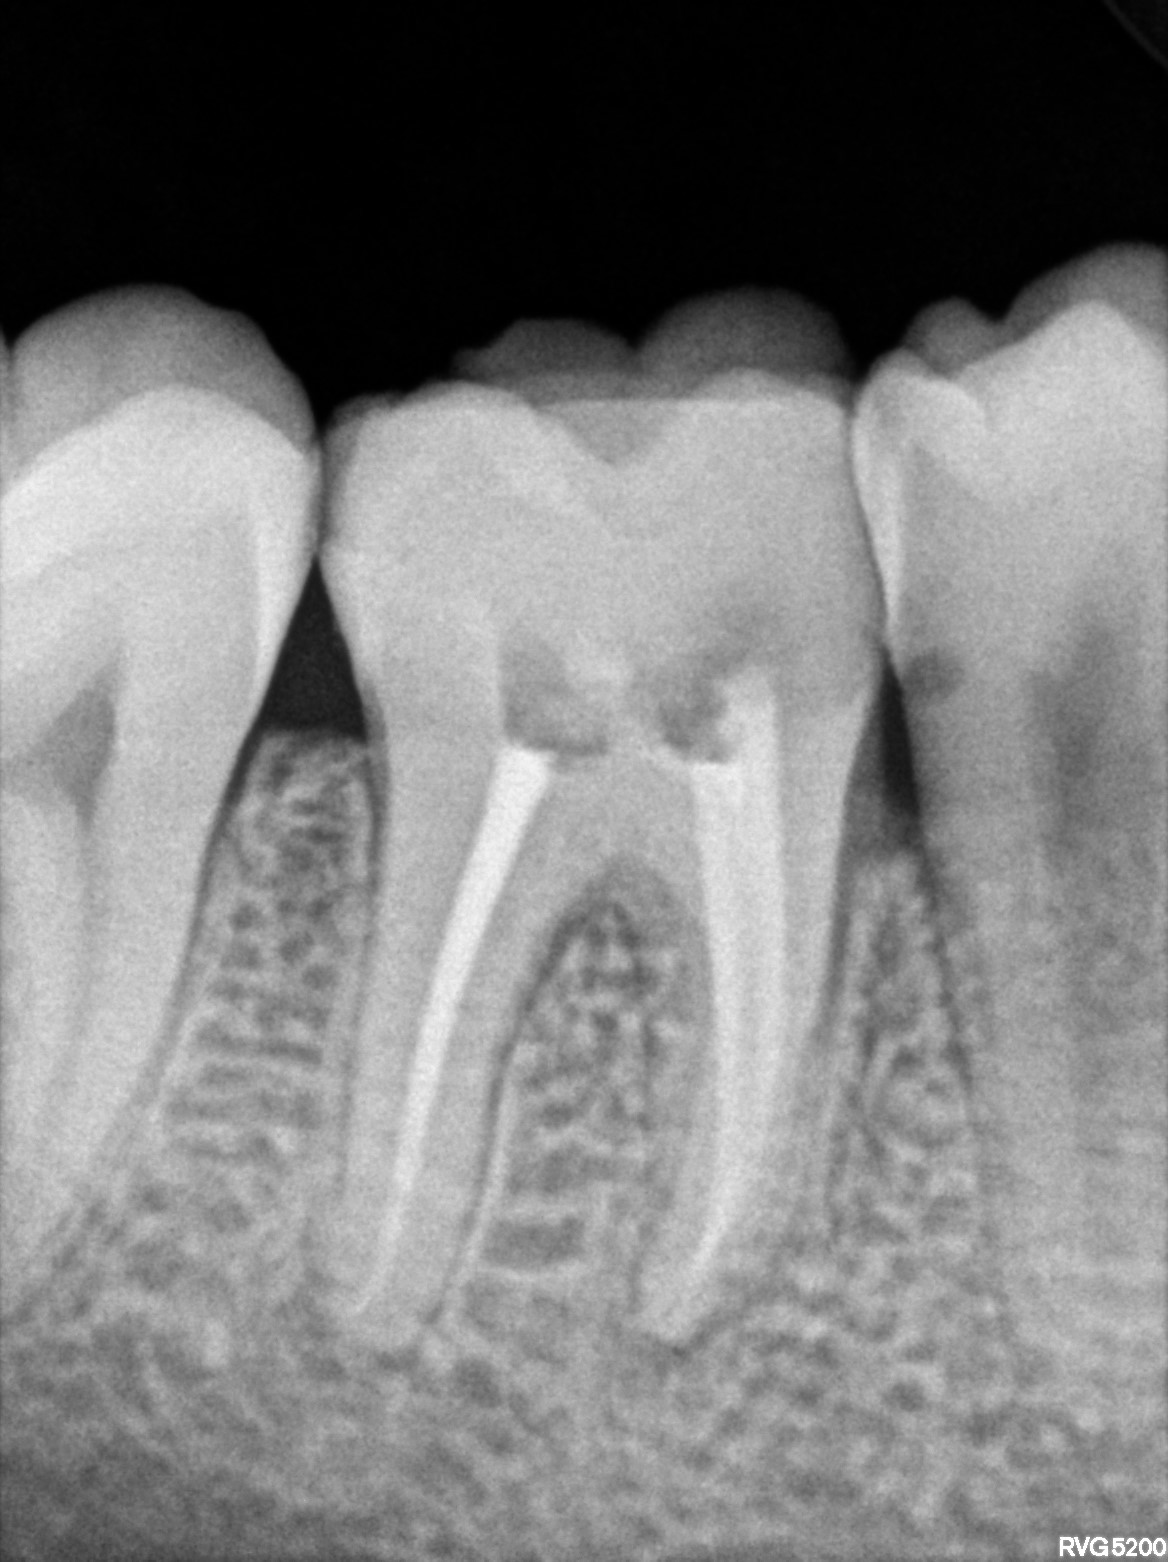

Dental Radiographs FHIR: DocumentReference · LOINC 24641-7

46.jpg

24641-7